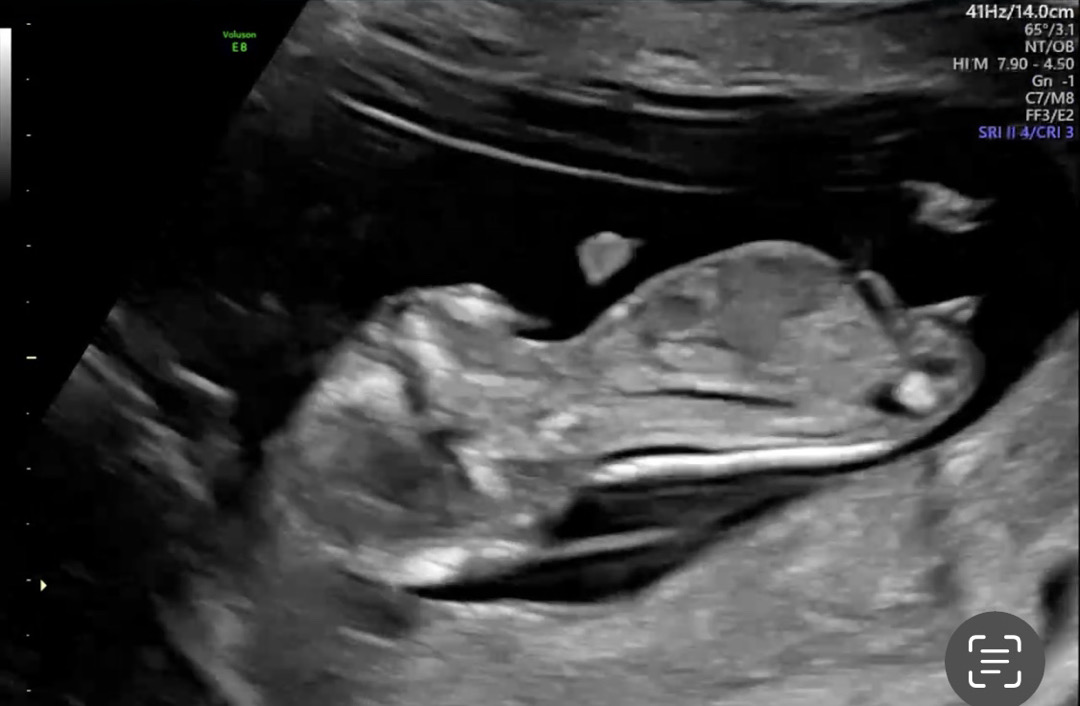

12주5일 각도법 봐주셔요! 감사합니다 ❤️